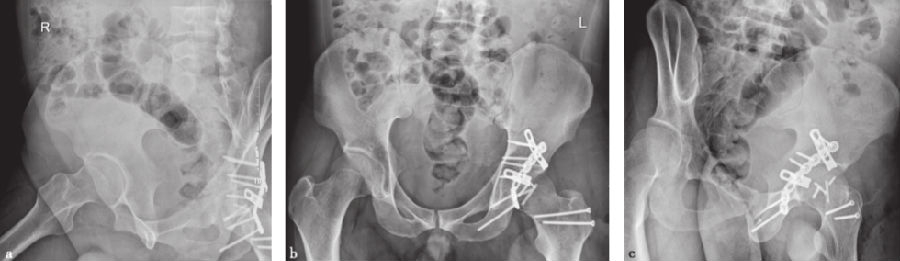

患者取侧卧体位,通过外科脱位技术(图7a~d),显露股骨头骨折的骨折面。直视下复位固定股骨头骨折后(图7e),使用Sprint接骨板固定髋臼后缘小骨折块,并用1块重建接骨板进行加强固定(图7f~h)。

图7 髋关节外科脱位典型病例手术过程a.患者取侧卧位,电刀烧出截骨线;b.大转子截骨后翻开;c.屈曲并内旋髋关节,显露前方关节囊;d.切开关节囊后,加大髋关节前屈和内旋,完成外科脱位;e.完成股骨头粉碎骨折的直视下复位和固定(其中一些粉碎的薄片已弃去);使用Sprint接骨板和重建接骨板对髋臼后壁骨折进行固定,术后拍摄闭孔斜位(f)、骨盆正位(g)、髂骨斜位(h)X线片确认复位及固定结果。

术后复查X线片提示(图7f~h):股骨头骨折解剖复位,髋臼后壁解剖复位。

术后头孢唑啉预防感染2天,体温正常,各项感染指标无异常。术后第7天出院。分别于术后8周、6个月、12个月复查X线片(图8),术后6个月的X线片见股骨头及髋臼后壁骨折均已愈合。术后12个月随访时患者髋关节功能良好,无疼痛,MRI见股骨头骨折愈合良好,无坏死(图9)。

图8 术后12个月X线检查a.闭孔斜位;b.骨盆正位;c.髂骨斜位。